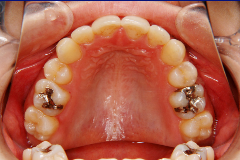

ステップ3. レントゲン (パノラマ,セファロ)撮影 口腔内写真撮影

口腔内写真,レントゲン

(必要に応じてCT)

ステップ3. レントゲン(パノラマ、セファロ)撮影・口腔内写真撮影

口腔内写真、レントゲン(必要に応じて CT )、印象(歯型)採得